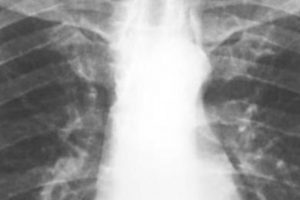

ASBESTOS IS still the number one cause of occupational deaths in the UK today, with over 5,000 recorded annually despite the fact it has been banned in the UK since 1999. However, Shawcity is delighted to announce the biggest advancement in asbestos technology for decades with the ALERT PRO 1000 from Alert Technologies.

ASBESTOS IS responsible for over 5,000 deaths every single year.

NEW FROM Shawcity, the ALERT PRO 1000 is said to be the world’s first early warning device for airborne asbestos fibres.